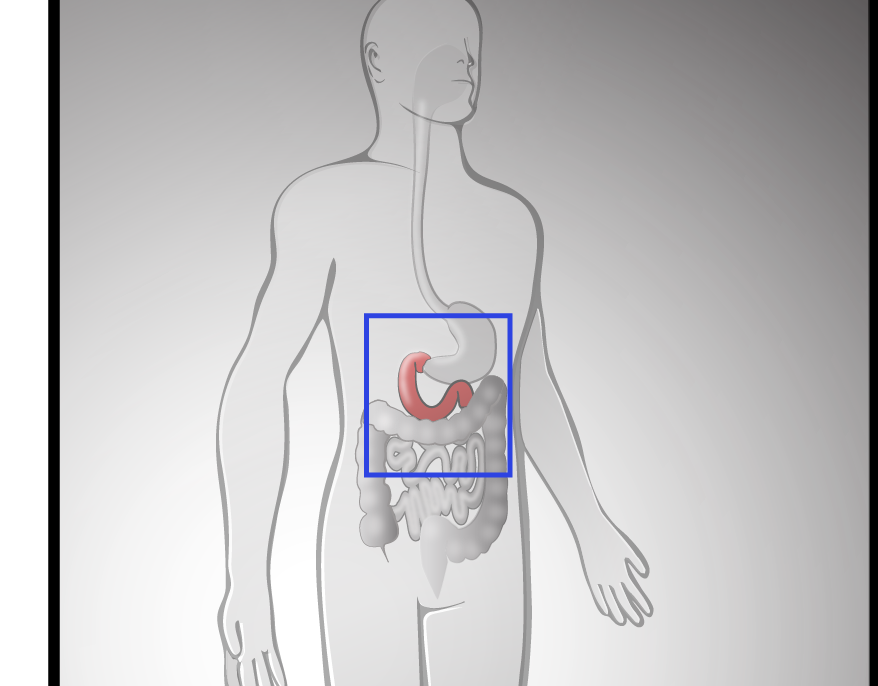

BioArt

Illustrating molecular method of action & drug delivery systems